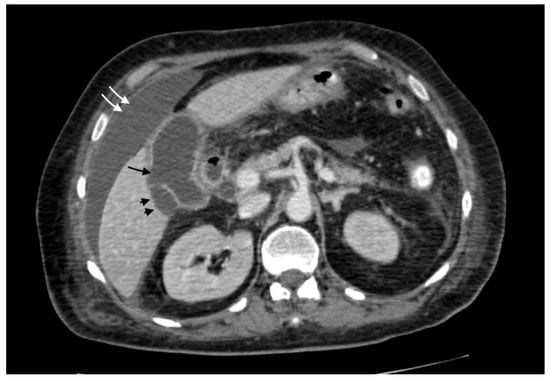

2.3.1. Gangrenous Cholecystitis

Gangrenous cholecystitis is a severe form of cholecystitis, characterized by transmural inflammation and wall ischemic necrosis. The risk factors include diabetes, alcohol abuse, male sex, and elevated white blood cell count [12]. The clinical presentation is similar to acute simple cholecystitis, though Murphy’s sign is more specific (100% vs. 63% in simple acute cholecystitis) [13]. The mean white blood cell (WBC) count is significantly higher and leans toward a gangrenous form against a simple form [13]. Radiologically, the presence of sloughed intraluminal membranes is characteristic. Other signs of inflammation seen in acute cholecystitis, such as wall thickening, pericholecystic fluid, and enhancement hepatic rim are often evident, as well as gallstones. Mural striations and decreased wall enhancement in a distended cholecystitis are other findings described in the literature, although not very specific [11]. A transmural defect in the gallbladder’s wall suggests perforation, a common consequence of this form (Figure 2).

Figure 2.

Gangrenous cholecystitis: irregular wall thickening with bulging and focal defects in the gallbladder wall (black arrows, (a)). Coexisting hepatic hyperemia (arrowheads) and pericholecystic fluid (white arrows) (a,b).